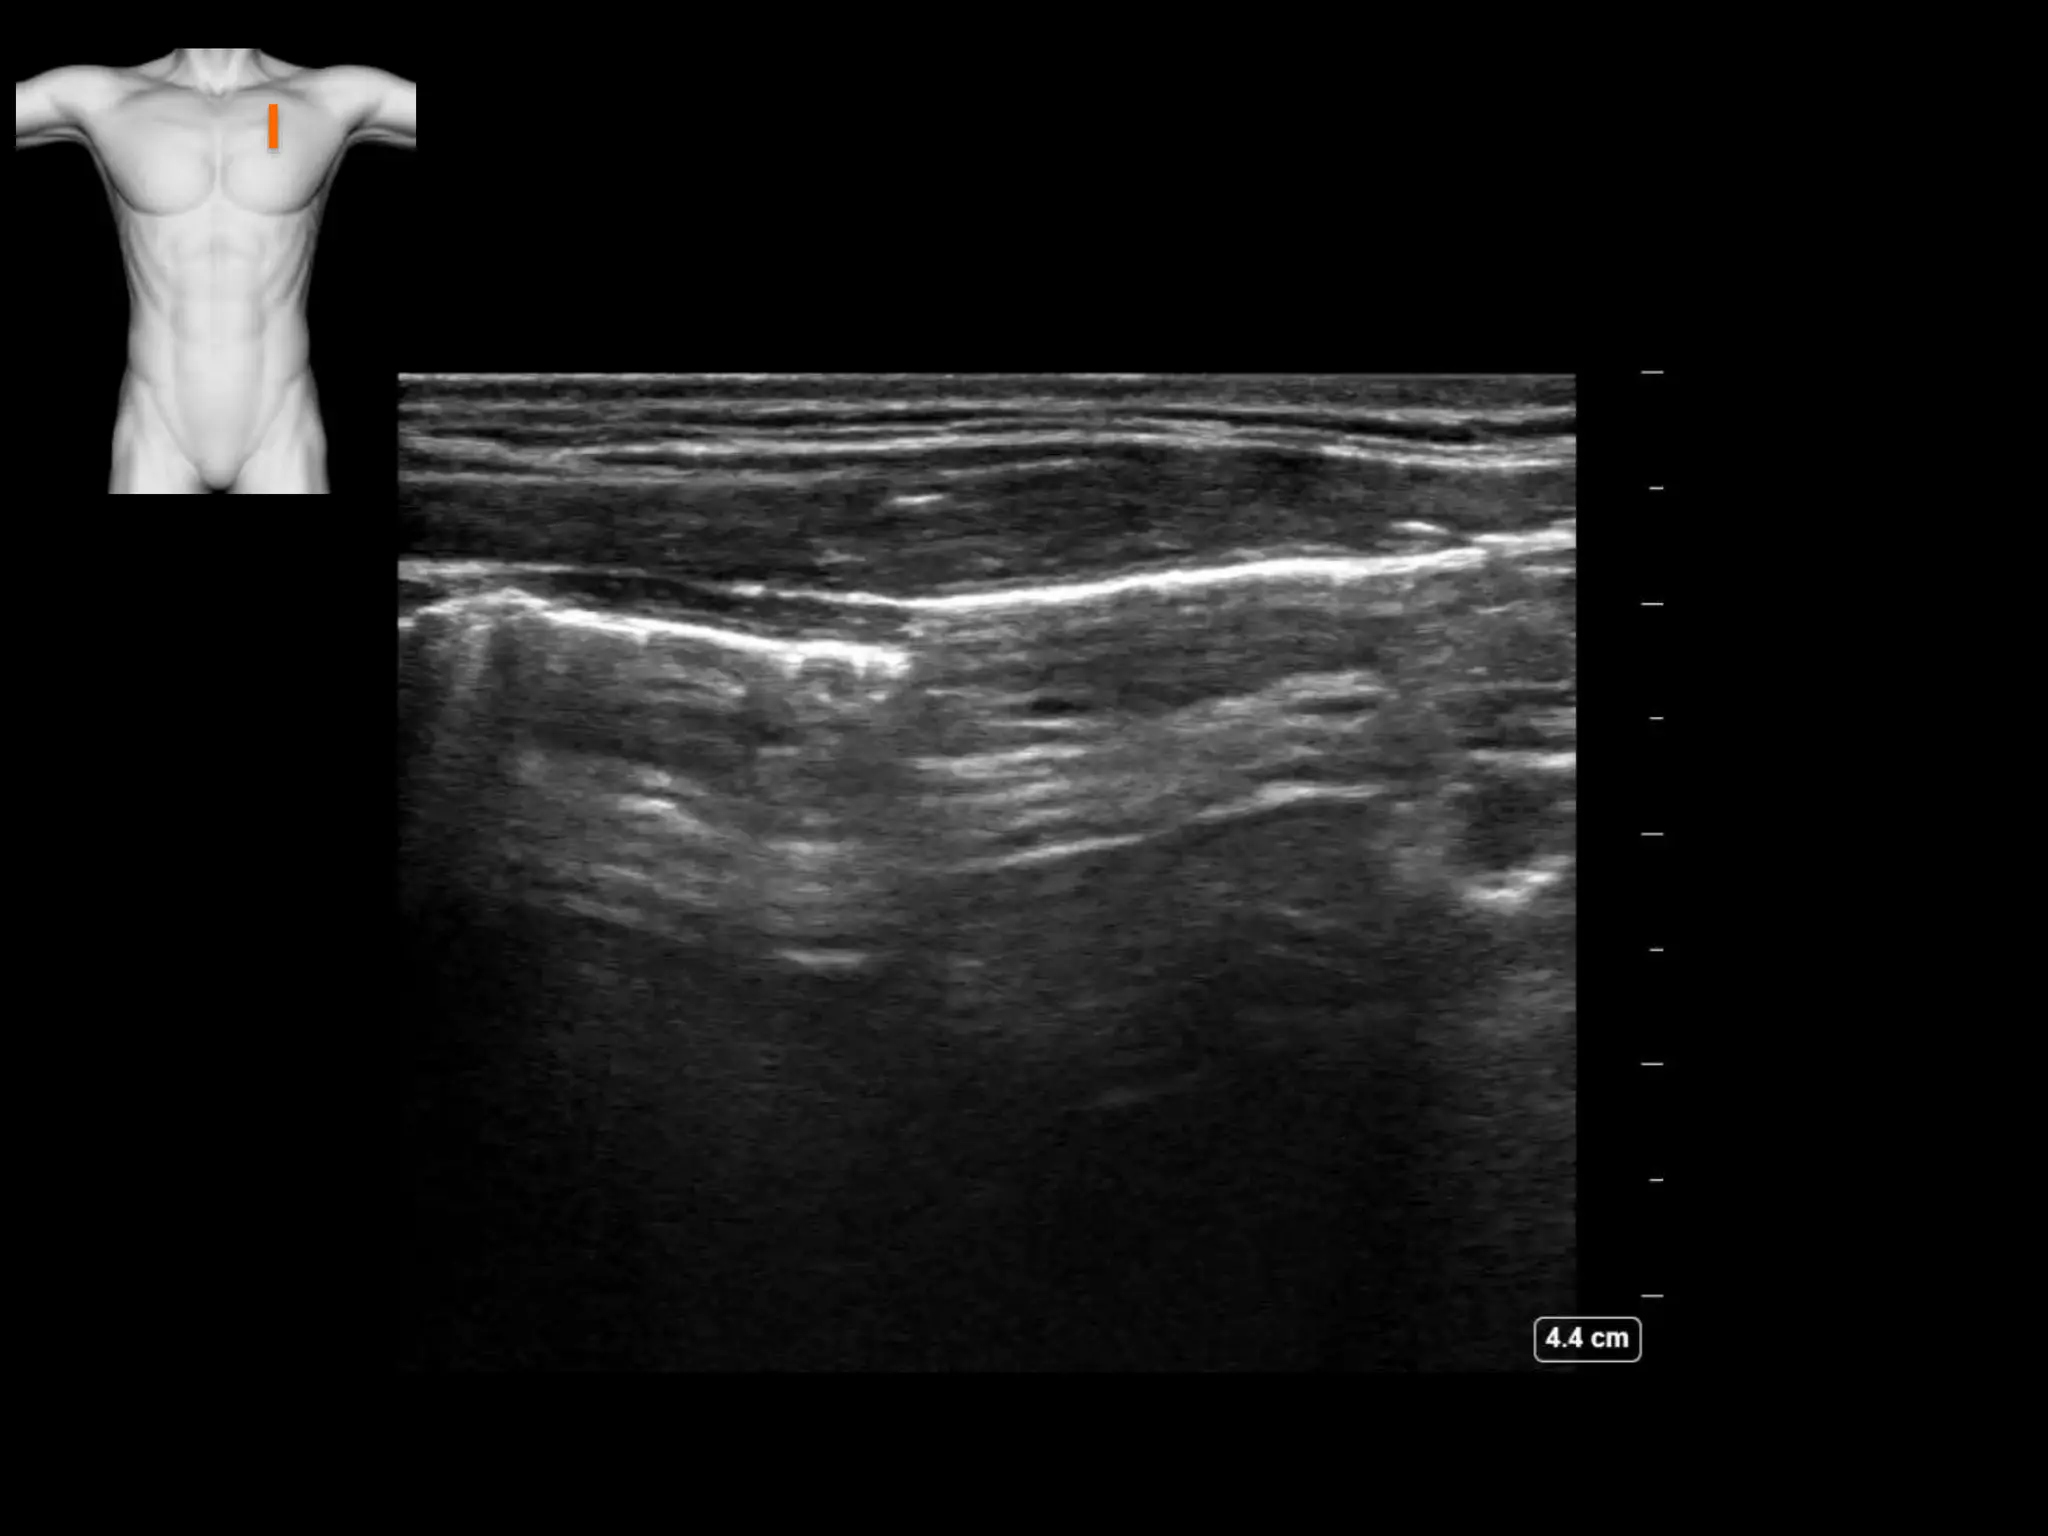

Subcutanous emphysema

• There is air lying between the facial planes

• No ribs are seen

• This is surgical emphysema obscuring true

interpretation of the underlying lung

Pneumomediastinum

• Here the carotid and IJ are briefly seen, with

surrounding air in the soft tissues